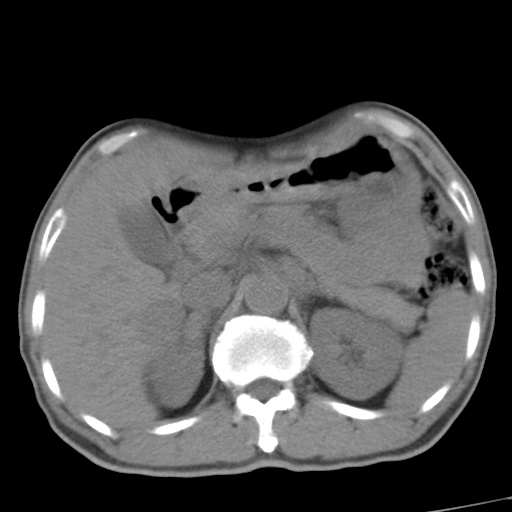

肝脏多发类圆形低密度影,考虑肝脏转移瘤,肝胃韧带一淋巴结肿大,原发?胃癌?

考虑胃癌并肝脏及腹膜后淋巴结转移;不排除淋巴瘤。

肝内转移瘤,腹腔及腹膜后淋巴结转移。